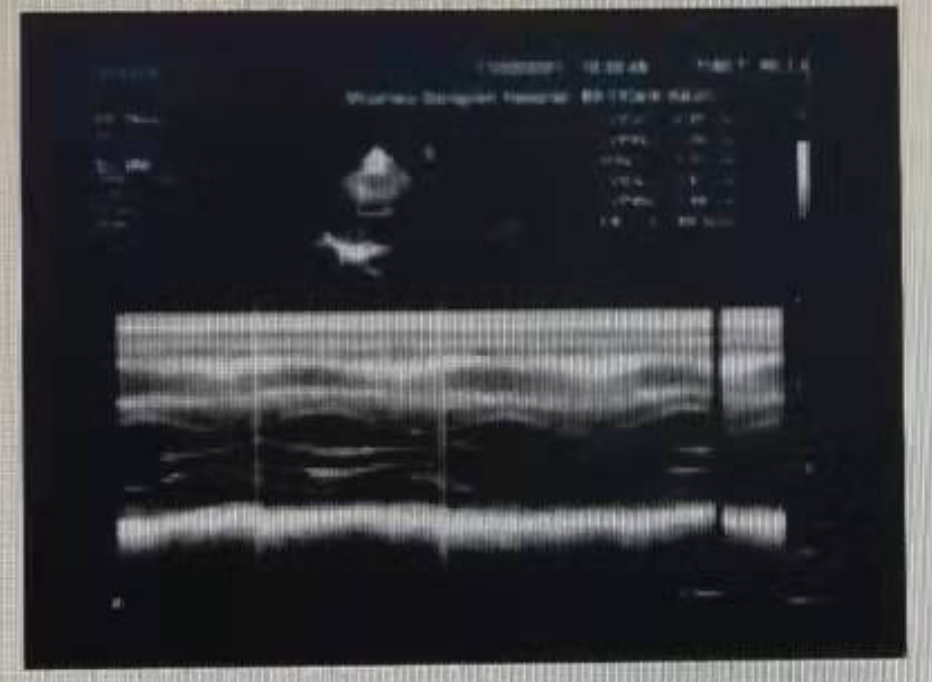

心脏超声

术后超声